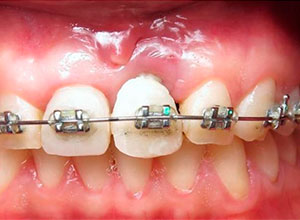

Se empezó a hacer la distracción, primero con un arco recto y posteriormente con elásticos haciendo el recorte con el borde incisal conforme se va bajando el implante con el bloque óseo.

Al término de la distracción dejamos pasar tres meses con una férula en acrílico. En el diente 21 que habíamos visto en la radiografía un problema de un absceso periapical y periodontal.

Nótese la colocación de los postes y el respeto a la forma de los tejidos gingivales y las papilas, muy importante para obtener el resultado estético final.

Nótese el manejo de las zonas papilares

Provisionalización para el manejo de tejidos blandos